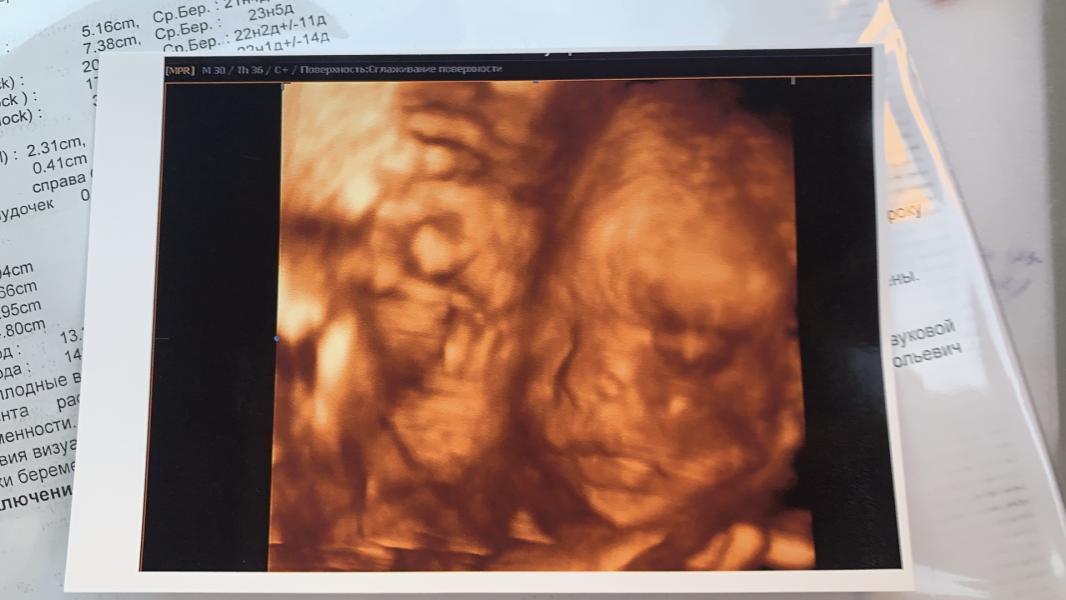

Сходили на узи!

Увидели нашего малыша.

Судя по фотографиям, копия меня.

От папы ничего не увидели, кроме причендалов🙈

На узи так же измерили носовую кость, для 22 недели 5,3 маловато. Отправили к генетикам из жк.😔

В узи 21 век сказали, что переживать не стоит, так как у меня нос маленький и все возможно что сына курносик будет, и все ещё догонит по развитию и кость подрастёт 🙏🏻